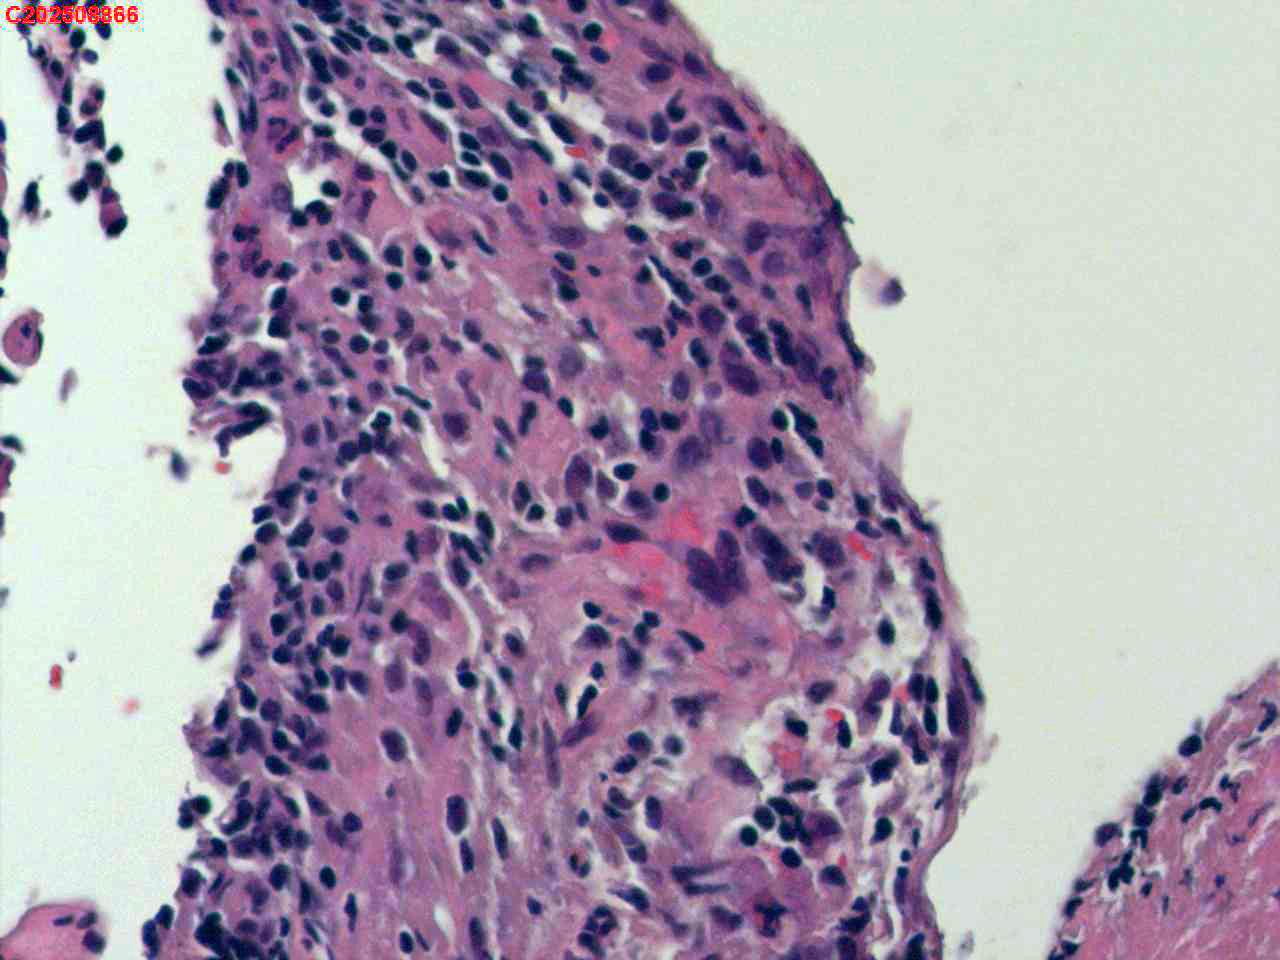

纤支镜咬检

肺TB?Ca?

胸部CT(平扫):考虑双肺感染性病变,结核?支气管炎?请结合临床及其它检查。

标本名称

右肺上叶后段开口咬检组织

大体所见

右肺上叶后段开口处粘膜不规则增生。

肉芽肿性炎的可能性大些!

有坏死,深染变形的细胞需要排一排神经内分泌肿瘤。